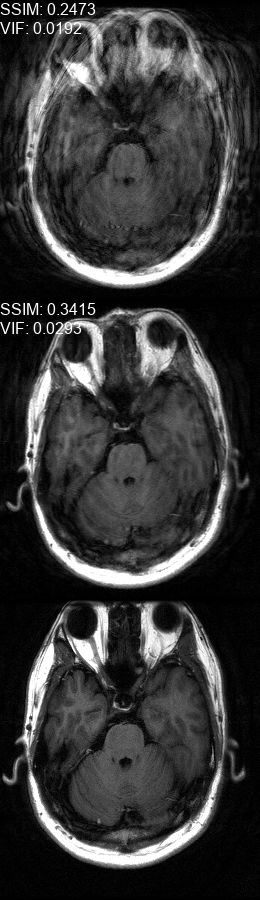

Fig. 5 contains four scan reconstructions from two patient cases. In both cases, the patient was requested to move at a certain time. In order to provide a ground truth for this scenario, another scan was performed using the same protocol for each patient, where the patient was required to hold still. The motion timing information for this case was obtained using the method described in [2] as it requires no additional hardware or changes to the scan protocol. We compare the reconstruction error using the SSIM [17] and the Visual Information Fidelity (VIF) [16] metrics, since a pixelwise comparison is not viable in this case.

Refer to caption

(a)

(b)

(c)

(d)

Figure 5: Examples of real motion corrupted images together with their motion corrected counterparts. The bottom row shows a corresponding slice from a motion-free acquisition of the same subject. These motion-free images were acquired using an additional scan. The images on the top row are motion-corrupted. Images on the middle row were corrected using our method. (a,b) motion was was detected at t1=96subscript𝑡196t_{1}\!=\!96, (c,d) the motion was detected at t1=112subscript𝑡1112t_{1}\!=\!112. All scans were acquired using 𝒮260subscript𝒮260\mathcal{FS}_{260} presented in Fig. 1b.